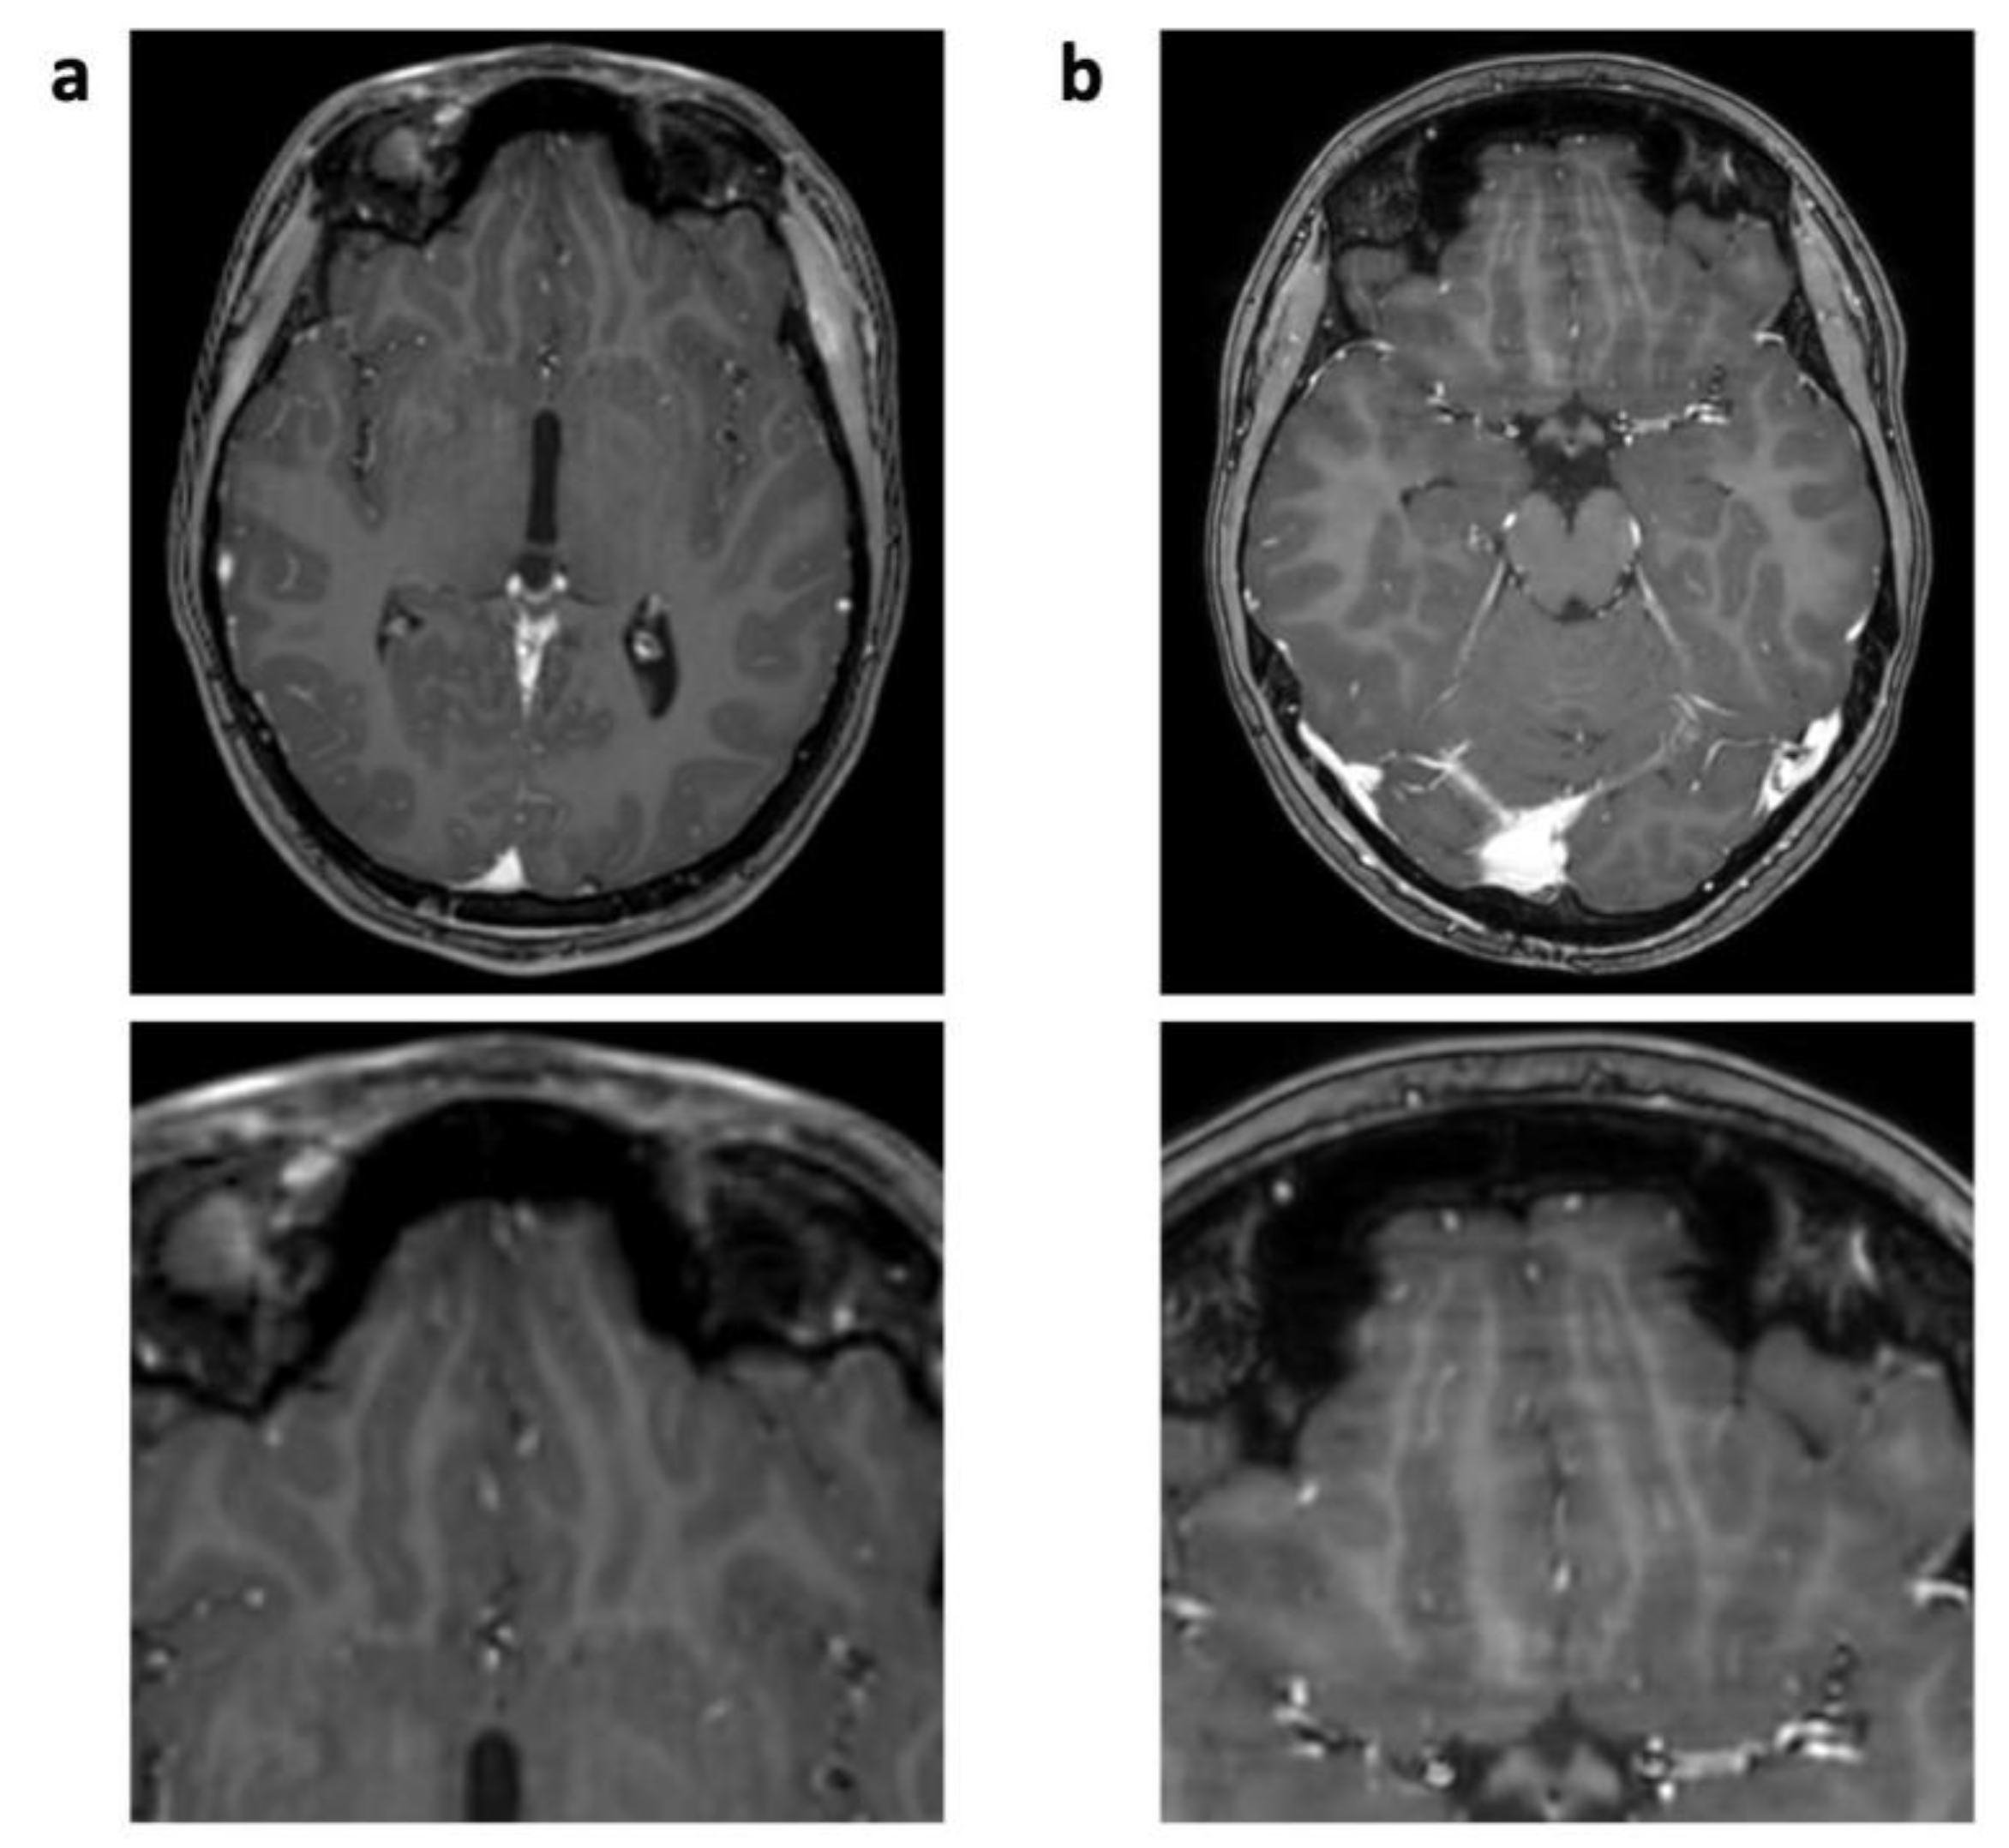

| Pulsation/ghosting | 17 (77%) | 23 (1.05 ± 0.72) | 0 | 0 | <0.001 | |

| Technique-related | Straight bands | 9 (41%) | 10 (0.45 ± 0.60) | 2 (9%) | 2 (0.09 ± 0.29) | 0.029 |

| Starry sky | 0 | 0 | 12 (55%) | 14 (0.45 ± 0.51) | ||

| Wax layer | 0 | 0 | 11 (50%) | 11 (0.50 ± 0.51) | ||

| Wavy lines | 0 | 0 | 2 (9%) | 2 (0.09 ± 0.43) | ||

| Overall | 5.73 ± 1.72 | 3.86 ± 1.21 * | <0.001 | |||